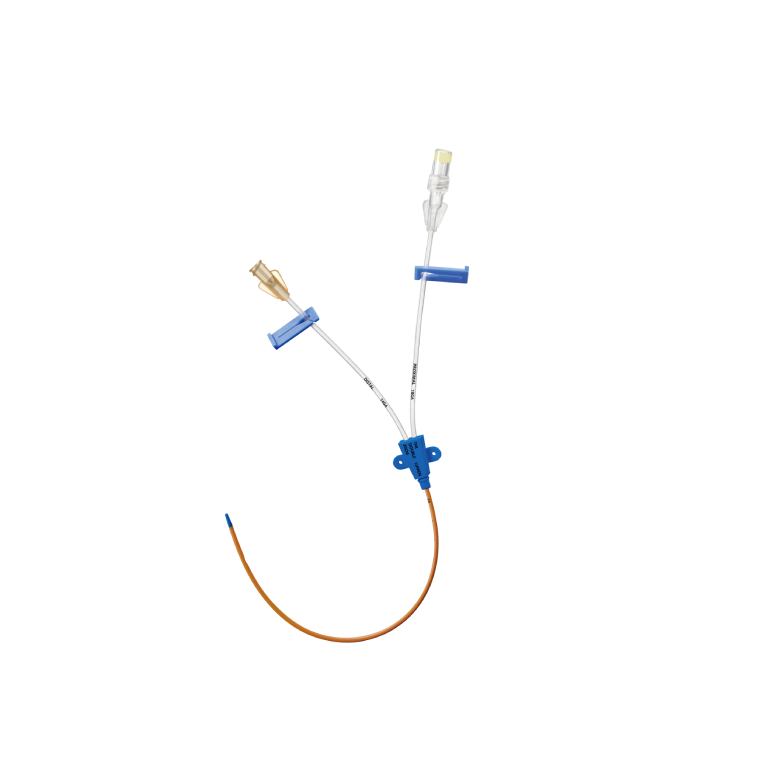

Lepu yüksek teknoloji tıbbi cihazlar ve ekipmanları

Kardiyovasküler tıbbi cihazlarda lider lepu medical, 190 iştiraki küresel bir ağa sahiptir. 214 ce sertifikalı ve 34 fda onaylı ürünle lepu, tıbbi cihazları, ilaçları, sağlık hizmetlerini ve kalp bakımı için mobil sağlık hizmetlerini kapsayan entegre bir platform kuruyor. Şirket sırasıyla 2009 ve 2022 yılında shenzhen borsası (300003) ve İsviçre borsasında listelenmiştir.